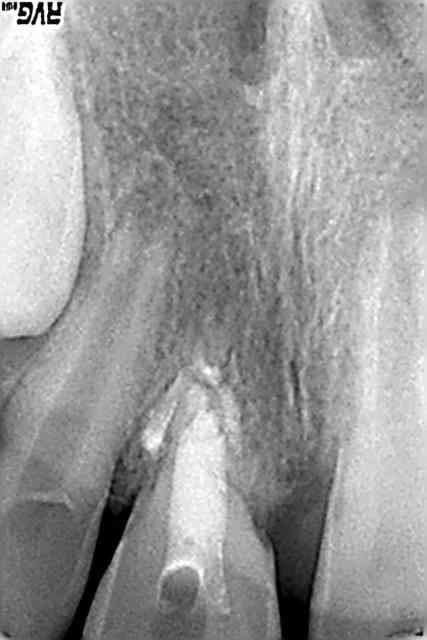

14/03/2007 à 21h25

radio ce jour

aucune inflammation

acune douleur

aucune mobilité

pour mémoire le ttt MTA date de novembre

il me semble que la rhizalyse continue?